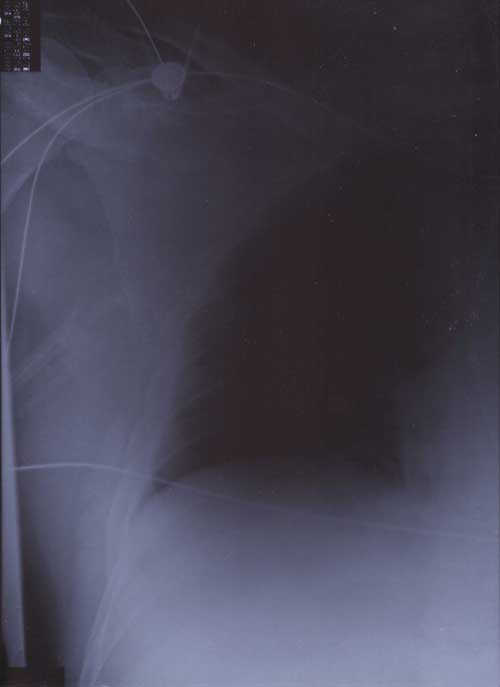

22nd January 2000